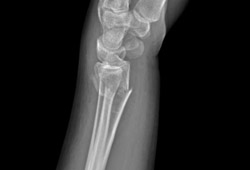

Fratura extra-articular do tipo A do rádio distal: vista lateral

Do acervo do Dr. Chaitanya S. Mudgal